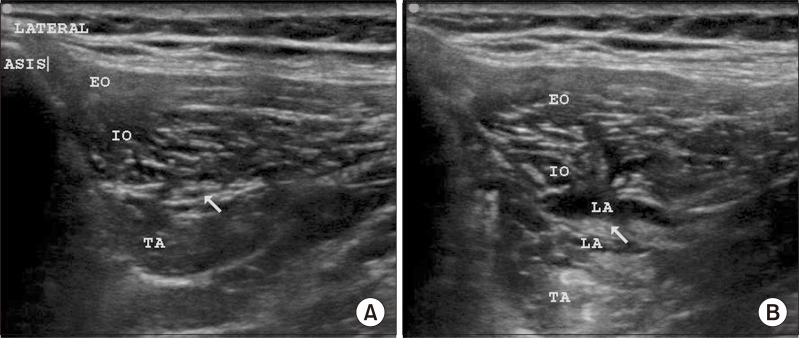

Methods: Seventy patients posted for inguinal hernia surgery were randomly allocated into group A (received ultrasound-guided II-IHNB with 10 mL of 0.5% ropivacaine and 4 mg [1 mL] dexamethasone) and group B (received ultrasound-guided II-IHNB with 11 mL of 0.9% normal saline). The time to first analgesic request, pain scores, opioid consumption, DN4 score, and PHGP at 3 and 6 months were analyzed using appropriate statistical tests.